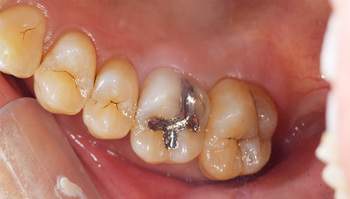

銀歯の中身の写真

麻布十番の歯医者さんで銀歯を外す前の症例写真

麻布十番の歯医者さんで銀歯を外す後の症例写真

こちらは銀歯を外す前と後の写真の比較になります。黒い部分が虫歯になっています。銀歯をつけているとなかなかレントゲンにも虫歯として映ってこないことが多いので、発見が遅れてしまうことがあります。